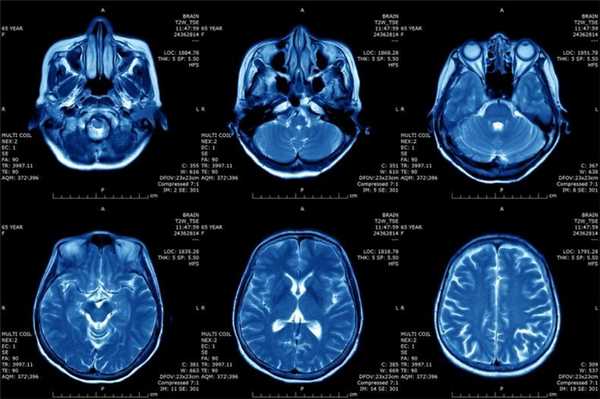

Что показывает МРТ

Магнитно-резонансная томография или МРТ - это сфокусированный метод, который проводит очень детальное обследование. Диагностическая точность МРТ превышает УЗИ и во многих случаях КТ, за исключением сканирования полых органов (легких, желудка, кишечника) и костей. МРТ является золотым стандартом диагностики:

- заболеваний головного и спинного мозга;

- патологий суставов;

- межпозвоночных дисков;

- сердца и сосудов;

- болезней гинекологического, проктологического и урологического характера.

В отличие от быстрого КТ и УЗИ, магнитно-резонансное обследование требует времени - в среднем пациенту нужно лежать в томографе и соблюдать неподвижность 30-60 минут.

Принцип работы МРТ основан на эффекте ядерного магнитного резонанса. МР томограф в своей конструкции имеет мощный магнит, который создает магнитное поле, и датчик, который подает радиочастотные сигналы. В такой ситуации протоны атомов водорода начинают колебательные движения, выделяя при этом импульсы. Их улавливает компьютер томографа и преобразовывает в трехмерные изображения. Чем больше воды содержится в клетках ткани, тем детальней получается ее изображение. Поэтому на МРТ хорошо отображаются органы с большим содержанием воды: МРТ головного мозга, МРТ спинного мозга, МРТ глазных орбит, МРТ органов малого таза, МРТ позвоночника, МРТ суставов, и плохо визуализируются органы с большим содержанием воздуха МРТ органов грудной клетки или кости.

Основы преимуществом МРТ перед КТ и рентгеном является отсутствие в ходе сканирования какого-либо излучения. А вот недостатком этого метода диагностики будет ряд ограничений - наличие ферромагнитного металла в теле пациента и имплантированных в организм водителей ритма, несовместимых с МРТ.

Магнитно-резонансная томография

В основе МРТ лежит явление магнитного резонанса, основанного на переизлучении радиоволн, взаимодействующих с атомами водорода, в избытке содержащимися в организме человека. Эти переизлученные электромагнитные волны улавливаются датчиком МР-томографа, усиливаются и в виде цифровых изображений появляются на экране монитора. Это безвредный и абсолютно безопасный для здоровья человека метод лучевой диагностики, так как в основе получения изображения отсутствует рентгеновское излучение, поэтому МРТ можно проходить неограниченное количество раз, с любым интервалом.

Существенное преимущество МР-томографии перед КТ заключается в том, что она не противопоказана беременным во II и III триместре и совершенно безопасна для детей. В МРТ исследуемая область сканируется в трех проекциях, что позволяет врачу-рентгенологу в полной мере оценить состояние тканей и органов исследуемой области, а высокая контрастность изображения и пространственное разрешение позволяют визуализировать серое и белое вещество головного мозга, оценивать состояние костного мозга и мягких тканей различной локализации. Кроме того, метод МРТ позволяет получать изображения сосудов головного мозга и сосудов шеи без введения контрастного препарата.